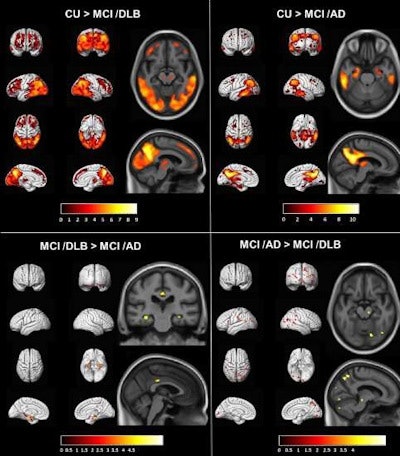

In this study, Kantarci and colleagues compared normal patterns of brain hypometabolism on FDG-PET with scans from groups of patients who progressed from mild cognitive impairment to dementia with Lewy bodies or Alzheimer's disease. They then compared the groups with dementia with Lewy bodies and Alzheimer's disease to identify any significant "metabolic signatures" between the groups.

Patients with mild cognitive impairment who progressed to dementia with Lewy bodies had widespread hypometabolism on FDG-PET compared with the normal group. The quantitative cingulate island sign ratio was higher in the group that had dementia with Lewy bodies compared to the group with Alzheimer's disease.

In addition, voxel-based analysis revealed higher FDG uptake in the posterior-mid cingulate region in those with dementia with Lewy bodies compared with patients with Alzheimer's disease, a finding that has not been demonstrated when comparing patients with these diseases, the authors noted.